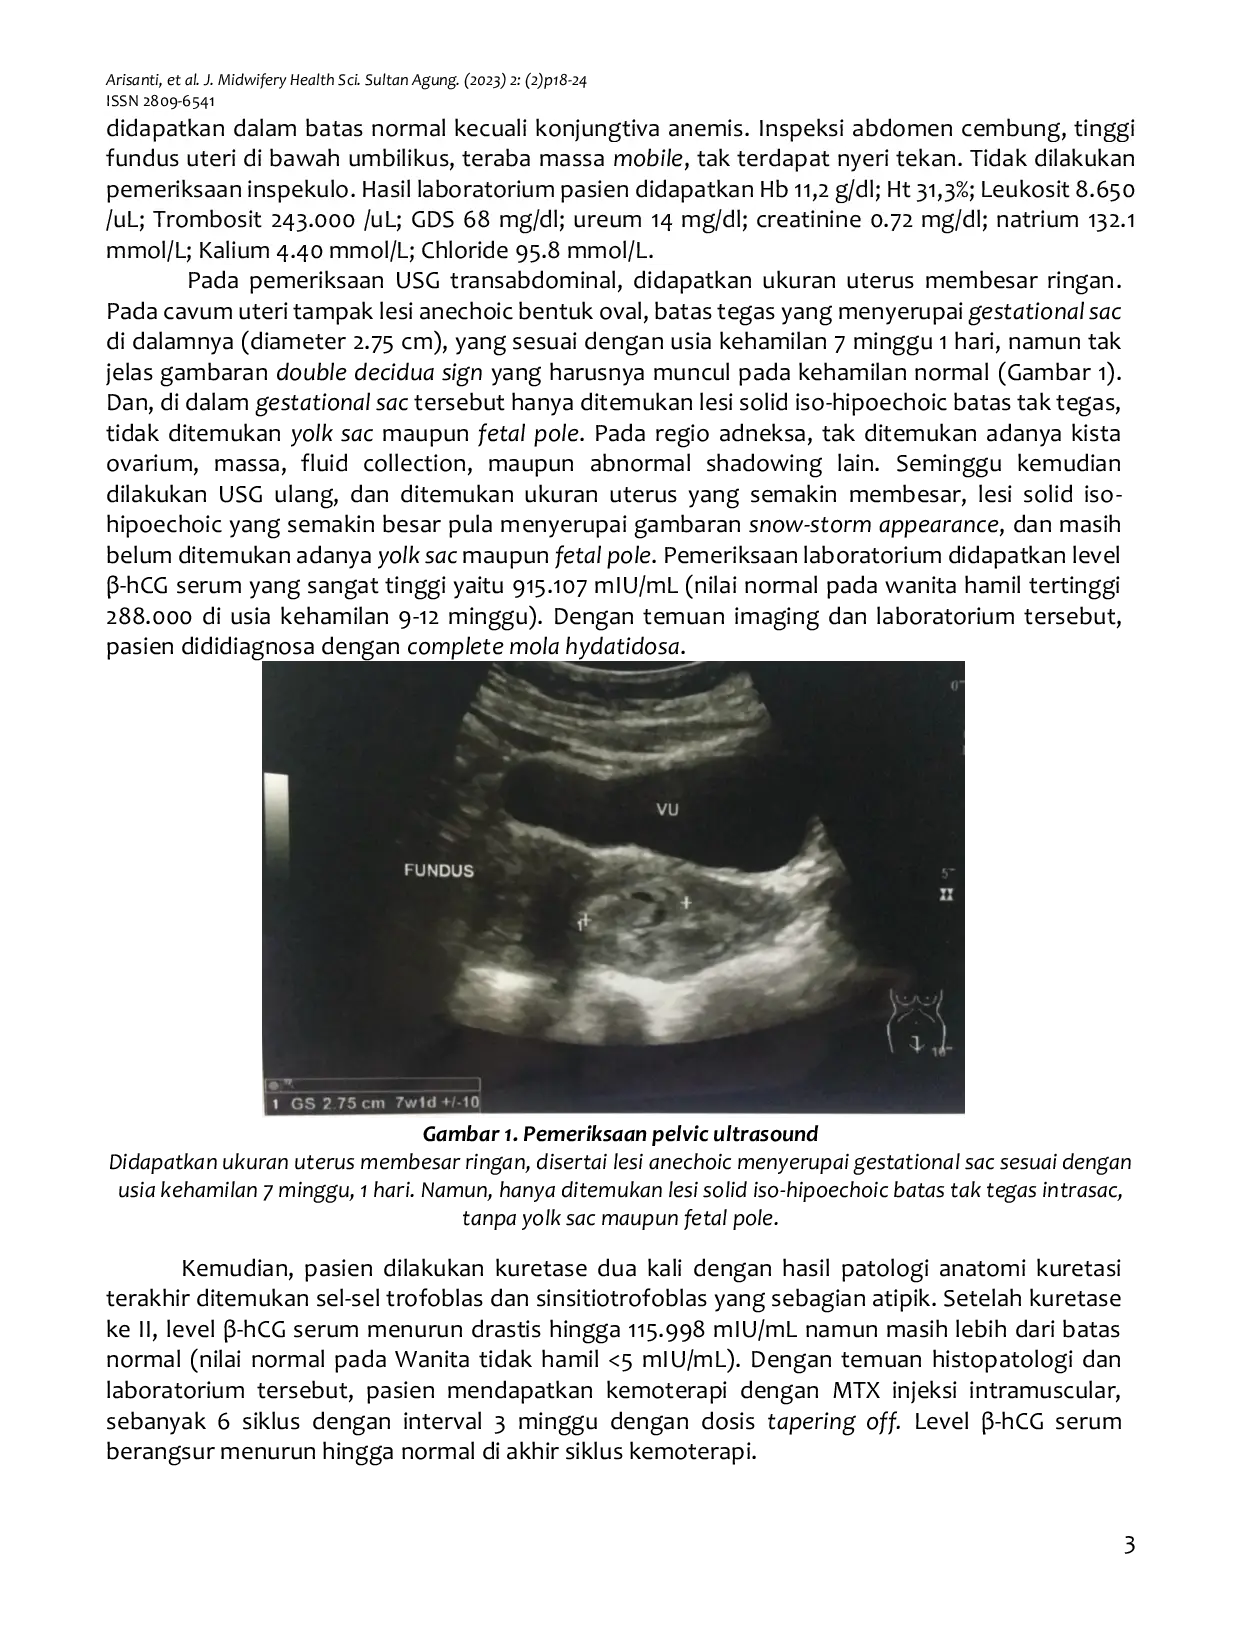

Journal of Midwifery and Health Science of Sultan AgungJournal of Midwifery and Health Science of Sultan AgungHydatidiform mole is a form of gestational trophoblastic disease (GTD) characterized by abnormal proliferation of trophoblastic tissue. It commonly presents with excessive uterine enlargement in early pregnancy and markedly elevated β-hCG levels. This report describes a case of complete hydatidiform mole in a 35-year-old woman, in which diagnosis was primarily established through characteristic imaging findings on pelvic ultrasonography. The patient underwent methotrexate chemotherapy, and clinical outcomes were monitored. The main outcomes included a favorable response to methotrexate therapy, evidenced by a decline in β-hCG levels and improvement of ultrasonographic findings. Cutaneous adverse effects were observed during treatment, manifesting as mucositis, papulovesicular lesions, melanonychia, and anagen effluvium.

Pelvic ultrasonography plays a crucial role in the diagnosis and follow-up of hydatidiform mole.Careful monitoring of methotrexate-related adverse effects, particularly cutaneous manifestations, is essential for patient safety.This case highlights the importance of integrating imaging, laboratory evaluation, and toxicity surveillance in the routine management of gestational trophoblastic disease.